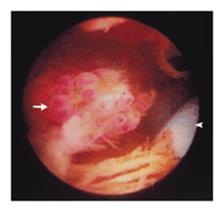

Gambar 6. Artroskopi menunjukkan

suatu pedunkulasi, lesi mirip anggur muncul dari sinovial pada lateral

parapatella (arrowhead) (MacDonald, et al., 1999).